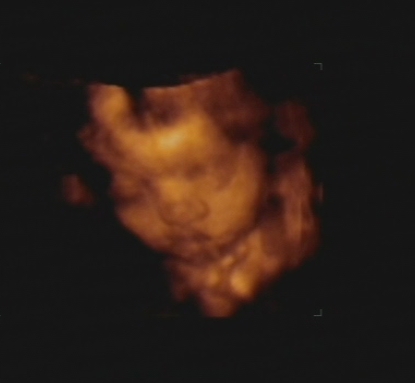

Swen, igen, határozottan maradt kislány 8) Úgyhogy Ildi, ruhacsere-akció lefújva :wink: :lol:

Rendben van minden a lánykával, bár sztem kicsit nagy a feje a mért adatok alapján...node nem parázok, mert arányosnak láttam a felvételen :) Meg a doktornő se mondta, hogy gáz lenne. Sikerült végre 4D-s képeket is készíteni! :D Remélem holnap fel tudom ide varázsolni.

Az apja szerint szép gyerek, még akkor is, ha az anyjára ütött :mrgreen: Elég nehéz volt rávenni a portréfotózásra – volt hátatfordítás, bicepszmutogatás, középső ujj feltartás, köldökzsinór arc előtti rángatása -, de végül engedett a kis drága :) Sőt, a végén - mintegy prezentálva, hogy Ő ezt már unja - egy kiadós ásítást is produkált :) Hjaj, úgy imádom!

Egyébként az adatai:

BPD: 7,22 cm

HC: 26,24 cm

AC: 21,8 cm

TAD: 6,6 cm

FL: 5,13 cm

Becsült súly: 1020 g.

Sikerült kimenekíteni egy képet a DVD-ből, íme az első sztárfotó :)